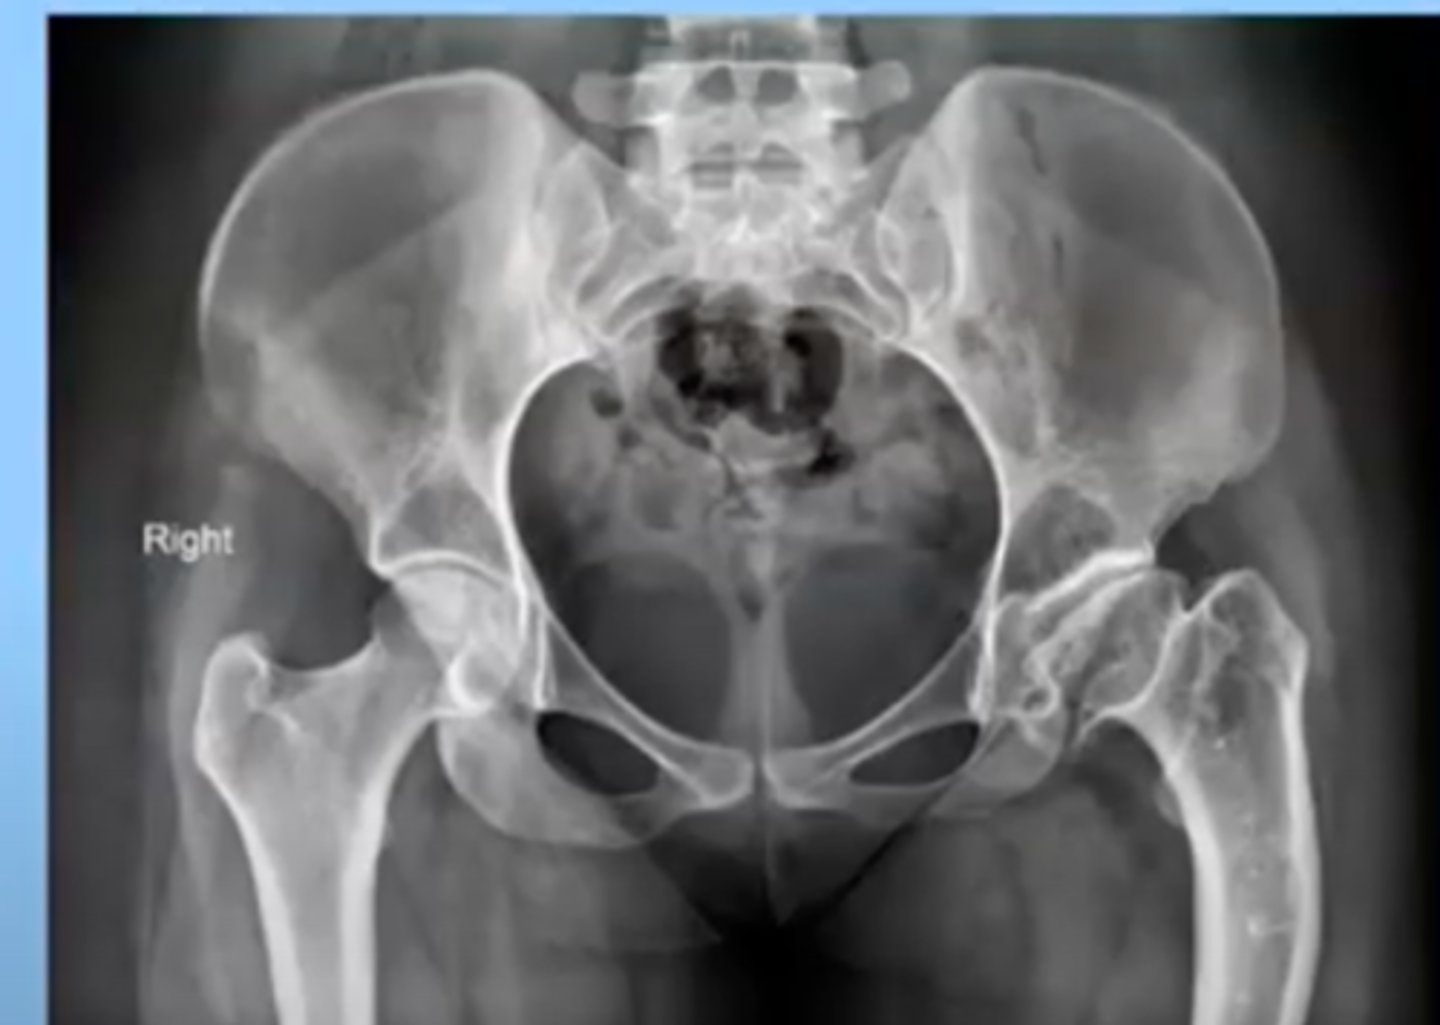

Avascular necrosis

Death of bone tissue because of a disruption in blood supply to the bone

femoral head of the hip is most common place

this can cause a fracture or be caused by a fracture or trauma to the bone (Acutely)

can also happen overtime

-ex: with a malignancy, chronic alcoholism, long term steroid use

-often have chronic pain in that area